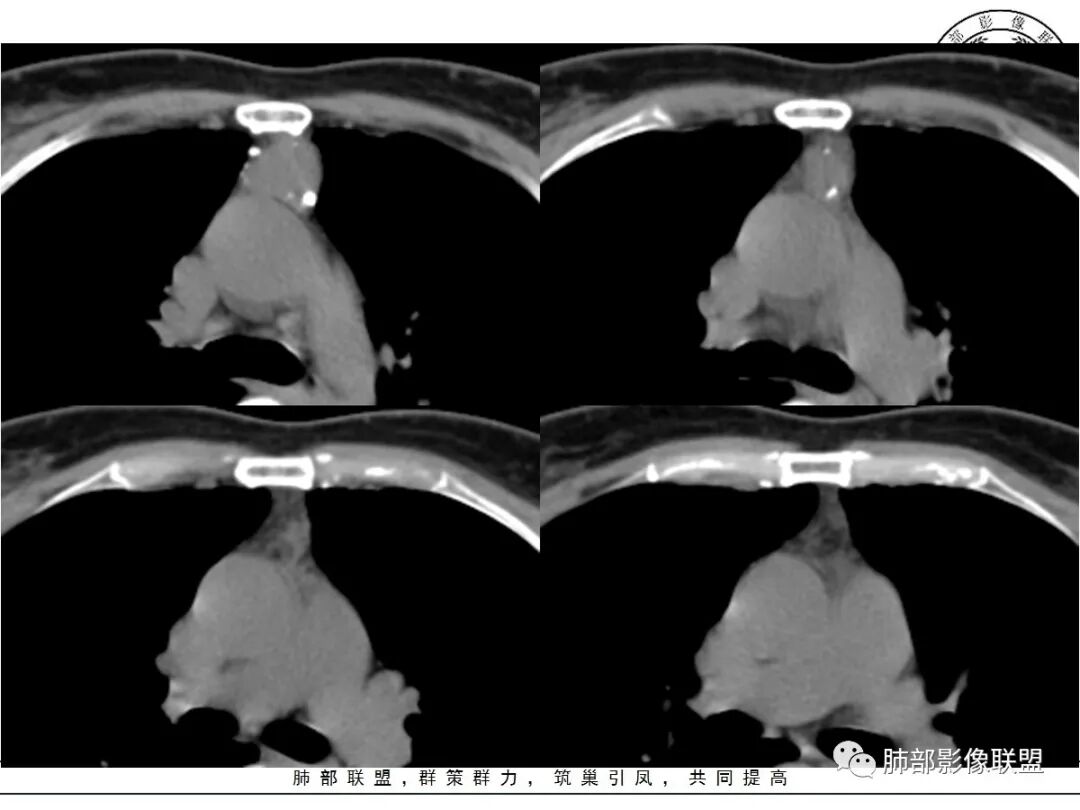

边缘多发条状、线样、结节状钙化

南边:边界尚清,位于残留胸腺组织内

前纵隔海绵状血管瘤的影像学特征包括:①发生于前纵隔的圆形、类圆形、不规则肿块影,边界清晰,与邻近结构分界清晰;②CT上呈稍低密度影,内见小结节状、小片状、针尖状的钙化灶,钙化灶、静脉石影是海绵状血管瘤的特征性表现。③增强后大多数肿块可显示肿块的范围及供血情况,动脉期病灶边缘呈点片状强化,静脉期及延迟期逐步向内填充,呈渐进性强化等典型特征,部分不强化或轻度强化,部分增强 后片状强化,强化程度与邻近血管相仿;血管瘤强化方式与肿块内组织成分、血窦内血栓、血流等因素有关;Moran等研究表明,肿块强化不均匀或呈轻度强化的原因可能与扩张的血窦腔内组织平滑肌增殖及炎性纤维化有关;肿块血管样强化可提示海绵状血管瘤。前纵隔海绵状血管瘤需与畸胎瘤、胸腺瘤、胸内甲腺肿、神经内分泌肿瘤等进行鉴 别 断:①畸胎瘤多呈混杂密度影,内有脂肪、毛发、钙化灶及水样密度;②胸腺瘤呈结节状、团块状影,密度较均匀,增强后强化较均匀,与周围组织分界清晰;③胸内甲状腺肿位于前上纵隔,平扫密度常较高,可见其上端与颈部甲状腺相连;④神经内分泌肿瘤多伴坏死囊变,点片状钙化,形态常呈分叶状或 不规则形,增强后肿瘤实性部分强化显著。

综上所述,海绵状血管瘤发生在纵隔非常罕见,且缺乏典型的临床症状及特异性影像, 应从肿块的位 置、大小、形态、与周围组织的 关 系 以及CT平扫、增强特点进行分析,如前纵隔肿块内有钙化灶、静脉石、增强后点片状血管样强化及渐进性强化等特点,应考虑纵隔海绵状血管瘤的可能;薄层CT及其多平面重组有利于发现细小钙化灶,而动态增强CT扫描能更好显示肿块内血管强化,有助于术前诊断与鉴别诊断。